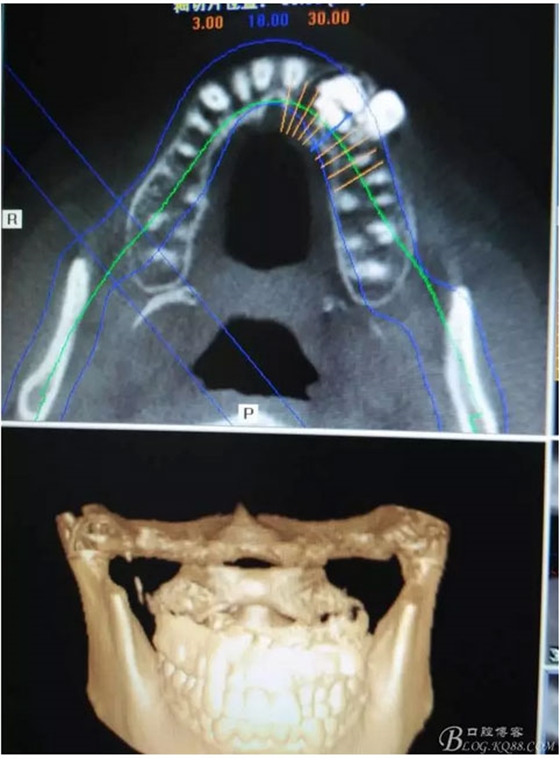

圖1。術前的CBCT影像檢查:22位于鼻底下方,23位于24、25的根方。左側(cè)乳Ⅱ、Ⅲ根方顯示囊性改變,囊腔內(nèi)大量致密鈣化團塊,密度高。